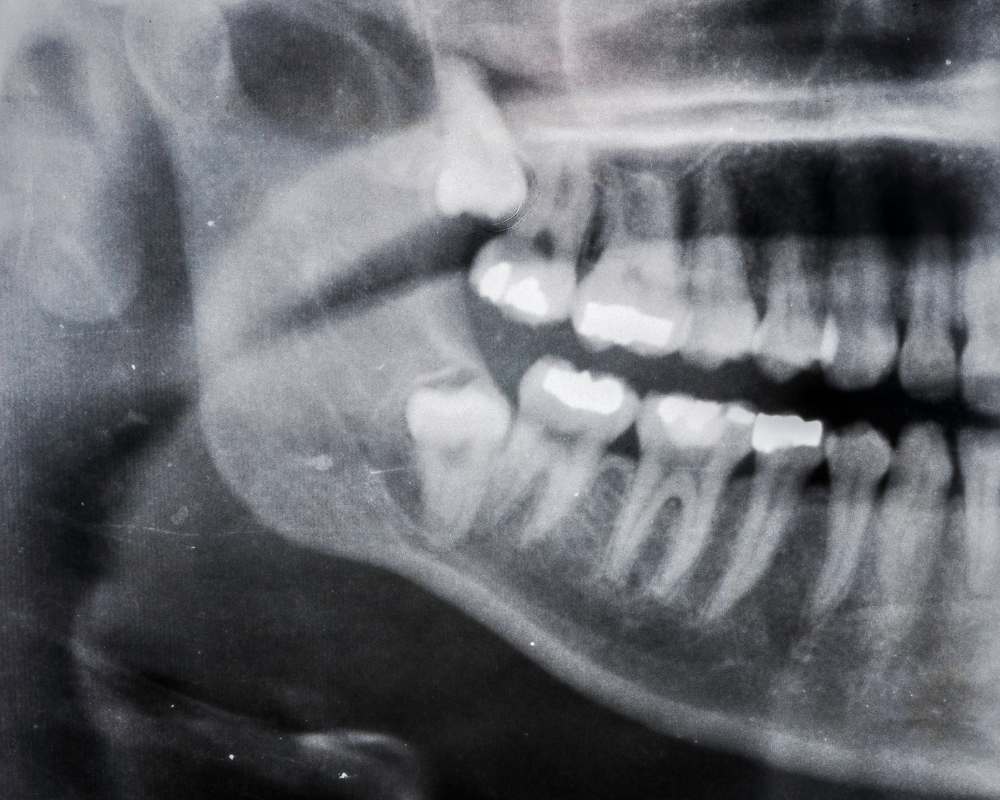

Impacted Wisdom teeth are very common and can cause abscesses, inflammation or damage to the molar in front of it. This often results in the wisdom tooth needing to be surgically removed.

Dr. Keith Chiang is an overseas trained Surgical dentist for 28 years with a formal Overseas Training Masters degree in Oral Surgery and offers professional expert care alongside IV sedation as well the latest technology using Digital Panoramic x rays, CT scans to study and diagnose your problem better.